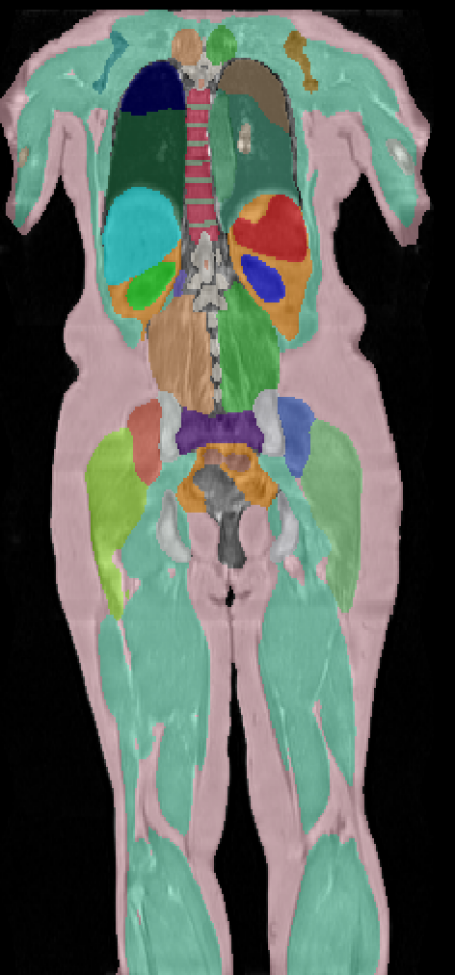

figureUKBOB Size and Diversity. Our proposed UK Biobank Organs and Bones (UKBOB) is the largest labeled medical imaging dataset for segmentation, comprising body organs of 51,761 MRI 3D samples (17.9 M 2D images) and a total of more than 1.37 billion 2D masks of 72 organs. Left: we show label examples from UKBOB from axial, coronal, and sagittal views. Right: We show a plot of the size (number of 2D images) and diversity (number of classes) of our UKBOB compared to other medical images datasets. The size of the bubbles indicates 2D image resolution. This new scale in dataset size and diversity should unlock a new wave of applications and methods in the computer vision and medical imaging communities.

We perform a series of experiments to determine the best segmentation model on UKBOB using state-of-the-art multi-resolution CNN (UNet[61], SegResNet[49], nn-UNet[26]) and transformer-based networks (TransUNet[7], UNetr[22], Swin-UNetr[21]). We report segmentation performance in Table VI where Swin-UNetr outperforms baselines by a margin, followed by nn-UNet. We show visual examples of the 72 class labels in UKBOB in Figure III and Figure IV.

We also show detailed baseline comparison for BTCV and AMOS in Table I and Table II respectively. We provide radar plot in Figure I that summarizes the performance of our segmentation model Swin-BOB compared to baseline segmentation models on different classes from BTCV and BRATS23 class average.